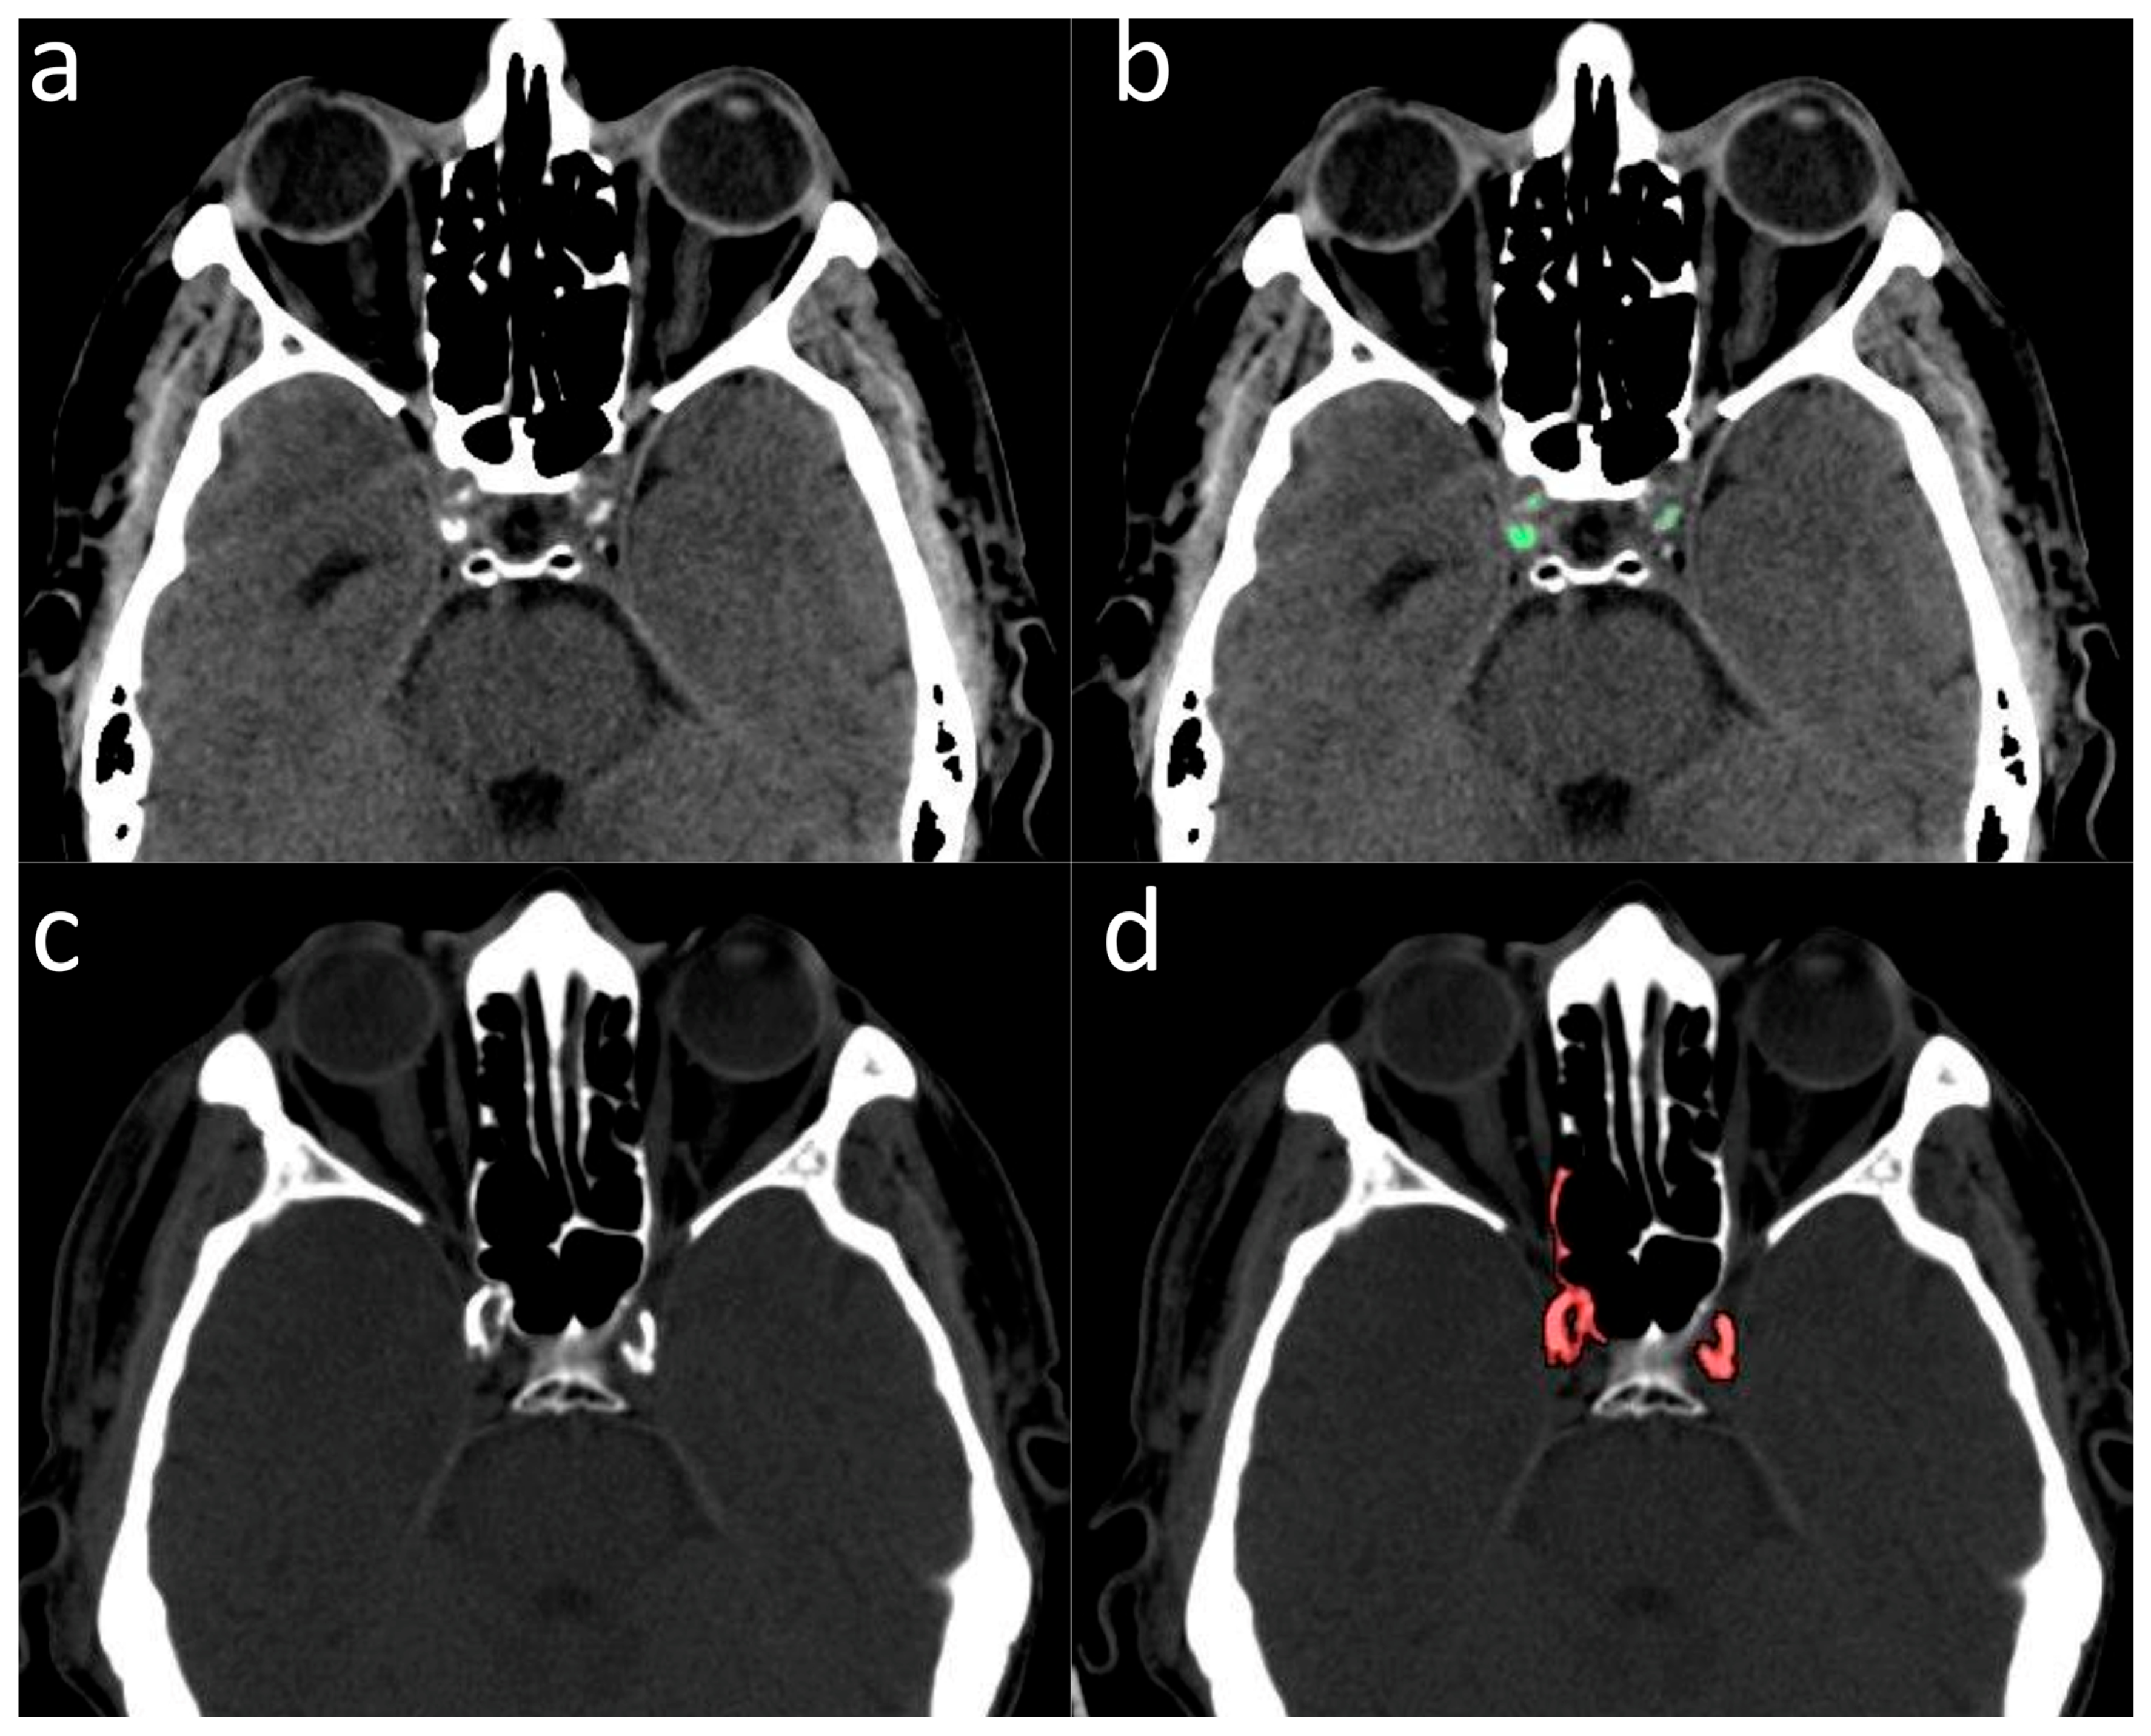

Data analysis was performed in August 2023. One hundred and ninety-six patients with GBM who met the enrolment criteria were identified from the Radiotherapy Department of Pisa University Hospital dataset. The ICA calcium scores were computed from brain CT images of GBM patients following the same procedure used for preliminary calcium score assessment in patients with lung cancer. Of them, 146 patients (74.5%) were excluded because of ICA proximity to the bony skull base, hindering an accurate quantification of ICA wall calcifications (Figure 1). Fifty patients (28 male, 22 female) were eligible for the final analysis.

Figure 1.

(a,b) Example of patient in whom the measurement of the ICA calcium score was feasible: (a) without calcium segmentation; (b) with calcium segmentation (highlighted in green). (c,d) Example of a patient in whom the measurement of ICA calcium score was not feasible due to overlap with the adjacent bony skull base: (c) without calcium segmentation; (d) with calcium segmentation (highlighted in red).